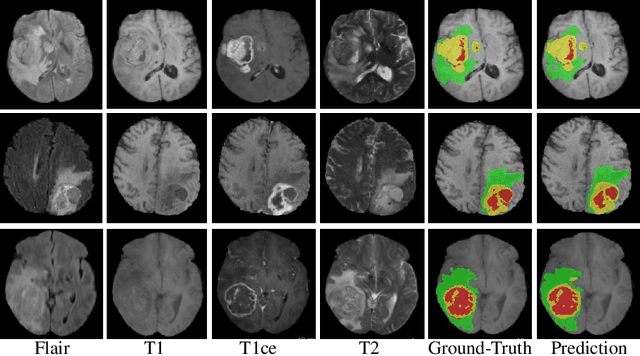

Abstract:In this work, we develop an attention convolutional neural network (CNN) to segment brain tumors from Magnetic Resonance Images (MRI). Further, we predict the survival rate using various machine learning methods. We adopt a 3D UNet architecture and integrate channel and spatial attention with the decoder network to perform segmentation. For survival prediction, we extract some novel radiomic features based on geometry, location, the shape of the segmented tumor and combine them with clinical information to estimate the survival duration for each patient. We also perform extensive experiments to show the effect of each feature for overall survival (OS) prediction. The experimental results infer that radiomic features such as histogram, location, and shape of the necrosis region and clinical features like age are the most critical parameters to estimate the OS.

Abstract:The accurate prognosis of Glioblastoma Multiforme (GBM) plays an essential role in planning correlated surgeries and treatments. The conventional models of survival prediction rely on radiomic features using magnetic resonance imaging (MRI). In this paper, we propose a radiogenomic overall survival (OS) prediction approach by incorporating gene expression data with radiomic features such as shape, geometry, and clinical information. We exploit TCGA (The Cancer Genomic Atlas) dataset and synthesize the missing MRI modalities using a fully convolutional network (FCN) in a conditional Generative Adversarial Network (cGAN). Meanwhile, the same FCN architecture enables the tumor segmentation from the available and the synthesized MRI modalities. The proposed FCN architecture comprises octave convolution (OctConv) and a novel decoder, with skip connections in spatial and channel squeeze & excitation (skip-scSE) block. The OctConv can process low and high-frequency features individually and improve model efficiency by reducing channel-wise redundancy. Skip-scSE applies spatial and channel-wise excitation to signify the essential features and reduces the sparsity in deeper layers learning parameters using skip connections. The proposed approaches are evaluated by comparative experiments with state-of-the-art models in synthesis, segmentation, and overall survival (OS) prediction. We observe that adding missing MRI modality improves the segmentation prediction, and expression levels of gene markers have a high contribution in the GBM prognosis prediction, and fused radiogenomic features boost the OS estimation.